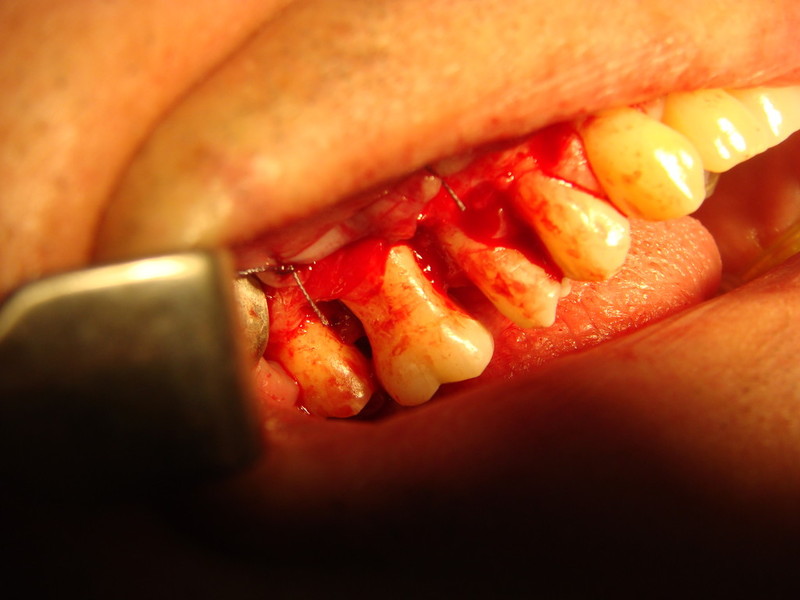

Rigenerazione difetto parodontale di un canino inferiore con materiale eterologo